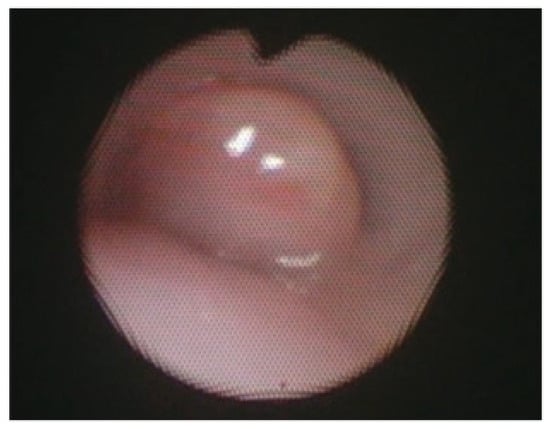

After successful posterior tracheopexy, posterior tracheal intrusion is greatly reduced, as most accurately depicted on postoperative bronchoscopy. These findings are also replicated when the technique is applied to more distal airway obstructive diseases, such as isolated right mainstem bronchomalacia (Figure 5). Secondary posterior tracheopexy has been shown to significantly improve respiratory symptoms, respiratory infection rates, brief resolved unexplained events, and ventilatory dependence (Table 2) [5,14,34,35,52]. Up to 90% of patients undergoing posterior tracheopexy experienced significant improvements in respiratory symptoms postoperatively including coughing, noisy breathing, and exercise intolerance [5,13,14,15,29,34,35,45]. The relative risk of respiratory infections was also reduced by >80% in larger case series [5,16,35]. Most patients are completely weaned from mechanical ventilation or noninvasive respiratory support postoperatively due to improved airway patency [14,16,22,35,52]. When performed primarily during TEF/EA repair, posterior tracheopexy has been shown to reduce TEF recurrence risk by up to 100% [39,48]. Furthermore, when performed primarily, patients may have a up to a 68% relative risk reduction in respiratory support dependence at 30 days and a 59% relative risk reduction in respiratory infections [3,7,8,11,42,52]. The operative time for secondary posterior tracheopexy may be as low as 161 min, but there are reports as high as 10.5 h [13,47]. This technique has a learning curve, and the presence of prior TEF/EA and/or esophageal leak with intrathoracic scarring may further complicate and prolong dissection. When performed primarily at the time of TEF/EA repair, the added time to perform primary posterior tracheopexy is reported to be as little as 6 min, which has not been shown statistically to significantly prolong operative times when compared to TEF/EA repair alone [2,7,22,42,46]. Those undergoing secondary posterior tracheopexy often have short ICU courses, relatively short hospital length of stays (often less than one week), and minimal resource utilization [11,49]. Incorporation of a minimally invasive approach can further reduce hospital length of stay to approximately three days in some studies [11]. In patients undergoing primary posterior tracheopexy, there is up to an 11 day reduction in median LOS compared to their counterparts who undergo TEF/EA repair alone, and there is no difference in perioperative complications between cohorts [2,7,42].

Figure 5.

Bronchoscopy of isolated right mainstem bronchomalacia before (A) and after (B) posterior right mainstem bronchopexy.